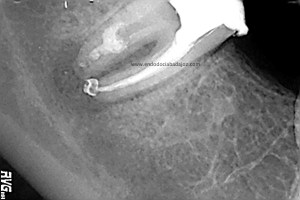

Este caso lo resolveríamos en varias sesiones, después del manejo de los conductos mesiales, con una preparación biomecánica terminando en una conicidad del 6% y un diámetro apical de 30 en conductos mesiales.

Bueno, pues el conducto distal se obturó en su tercio apical y medio con M.TA.